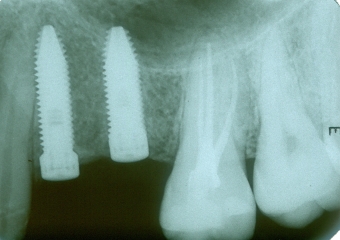

Rx mostrando a ausência de dois pré molares superiores

Raio X dos implantes instalados